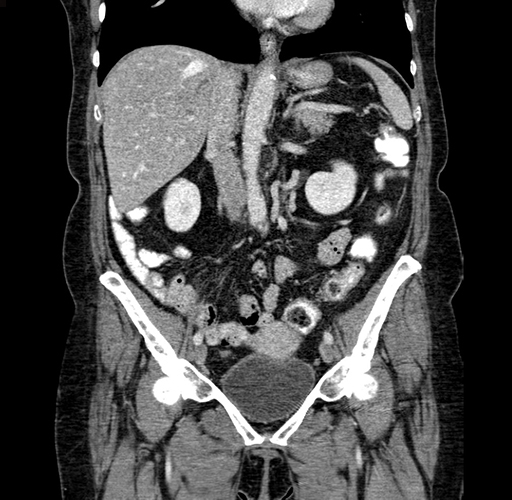

Pre-Chemo: Coronal Venous

Coronal Venous